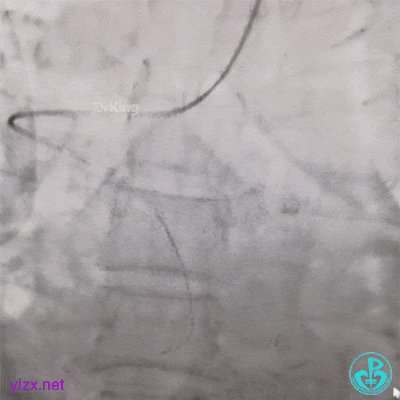

现在时间充裕,解决腿上打折的管子。

J-W软头端无法通过管子。

换硬头端(铤而走险、不常规推荐)。

管子头还是打不开,调整一下。

打折处通了,换软头端(直头端不敢出GC)。

管子头段直啦。

拉出来了。